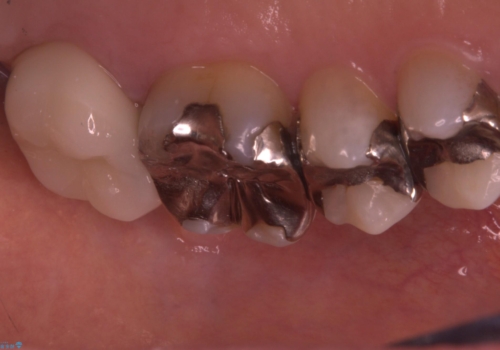

- 主訴:詰め物と歯の境目に穴が空いているとクリーニング時衛生士から指摘された。

保険適用のメタルインレー歯質の境目が虫歯になっていたため、一度メタルインレーを除去し虫歯の範囲の把握と補綴物のやり替えをお勧めし、ジルコニアクラウンでのやり替えとなりました。

保険適用のメタルインレーと歯質の境目にう窩ができており、補綴物のやり替えとなりなした。